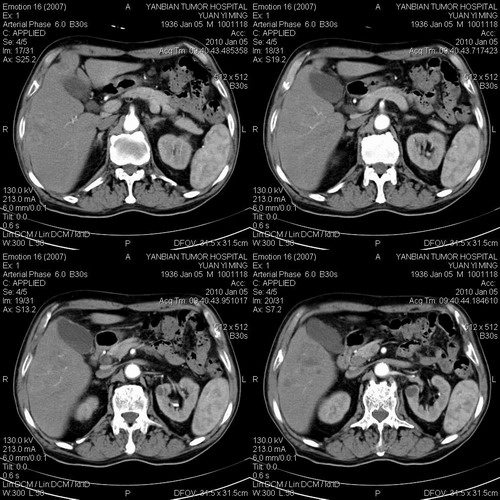

标题: CT24024:男,74岁。体检超声发现肝内多发占位性病变四天。 [打印本页]

标题: CT24024:男,74岁。体检超声发现肝内多发占位性病变四天。

并肝肾囊肿。

1)考虑肝脏恶性肿瘤(转移瘤?)。2)肝外胆管轻度扩张。3)左肾小囊肿。

考虑肝脏恶性肿瘤(转移瘤?)。2)肝外胆管轻度扩张。3)左肾小囊肿。